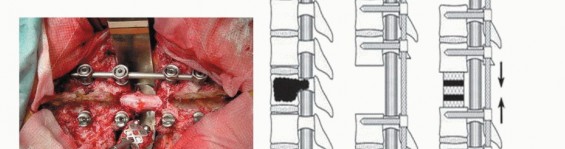

5. Anterior Reconstruction and Posterior Instrumentation

An anchor hole on the cut end of the remaining vertebra is made on each side to seat the graft. A vertebral spacer such as a titanium mesh cylinder cage with autograft, allograft, or cement(TECH FIG 6) is properly inserted to the anchor holes within the remaining healthy vertebrae. After checking the appropriate position of the vertebral spacer radiographically, the posterior instrumentation is adjusted to slightly compress the inserted vertebral spacer. By this “spinal shortening” procedure, the block cylinder is caught tightly, and the anteroposterior 360-degree spinal reconstruction is completed. 2,7 If two or three vertebrae are resected, it is recommended that the connector device be applied between the posterior rods and anterior spacer (artificial pedicle).

TECH FIG 6. A. A vertebral spacer is properly inserted to the anchor holes within the remaining healthy vertebrae. B. Schema of reconstruction (lateral view). C,D. After checking the appropriate position of the vertebral spacer radiographically, the posterior instrumentation is adjusted to slightly compress (10 mm in this case) the inserted vertebral spacer. E,F. Postoperative radiograph after spinal column shortening shows three pairs of preoperative embolization coils. (continued...)

TECH FIG 6. (continued...) G-I. Resection of two vertebrae. G. Bilateral artificial pedicles are placed. H,I. Postoperative radiographs of reconstruction with artificial pedicle.

Spinal shortening

- The posterior instrumentation is adjusted to compress the inserted vertebral prosthesis slightly (5-10 mm) to secure it as a final step of spinal reconstruction using TES.

- This process of spinal shortening provides two important advantages: (1) increased spinal stability of the anterior and posterior spinal column and (2) increased spinal cord blood flow, which is desirable to improve spinal cord function.